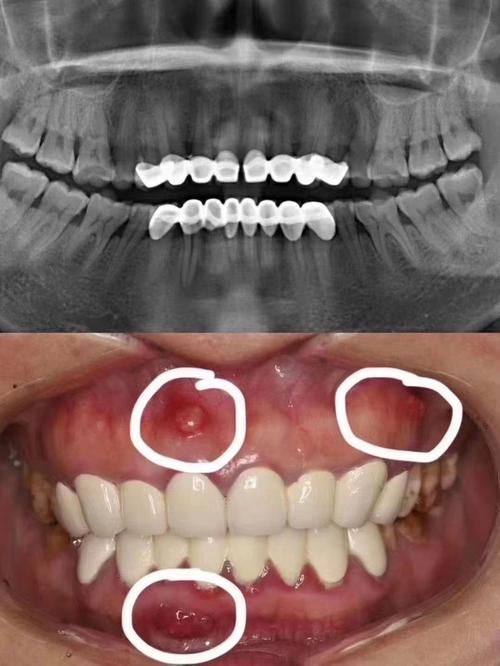

门诊部还引进了众多高端新型的口腔医疗设备,如德国卡瓦种植机、美国3shape口腔扫描仪、意大利NewTom CT等。以种植牙为例,传统种植依赖医生经验,而新桥口腔引入的数字导板技术,能通过CT扫描生成患者口腔三维模型,医生在电脑上提前规划种植位置、角度和深度,手术时像“导航”一样精细,创伤小、修复快,尤其适合牙槽骨条件差的患者。正畸治疗中,iTero口内扫描仪5分钟就能获取牙齿3D数据,患者当场就能看到矫正后的结果模拟,避免了传统取模的异物感和等待时间,儿童患者也能轻松配合。

德阳新桥口腔门诊部汇聚了一大批口腔医学领域的佼佼者。马燕主医师是新桥口腔种植专科的领头者,以其深厚的种植修复技术和独到的美学理念著称,擅长各类复杂的种植修复治疗。陈刚技术总监是新桥口腔外科领域的显要人物,擅长龋病、牙髓病、根尖病的精密诊断与治疗,尤其在根管治疗、根尖外科手术方面有着极高的造诣。易华波主医师以其多方面的口腔修复技术和实力强的种植技术出名,特别是在半口/全口即刻负重种植修复领域有着深厚的造诣。

此外,还有孙玉枫医生,师从国内出名种植医师刘果生,擅长即刻种植、小创口种植和美学修复,拥有登腾种植操作、盖氏骨增量等多项海内外认证,临床经验充足,能根据患者牙槽骨条件设计个性化方案;赵丹医生,是3D数码隐形正畸(隐适美、时代天使)双认证医师,擅长龅牙、地包天等复杂矫正,能精密调整咬合关系,让患者笑得更自信。而且医院实行“总院医师定期坐诊”制度,遇到疑难病例时,成都总院的医师会直接到德阳分院会诊,确保治疗方案的科学性。